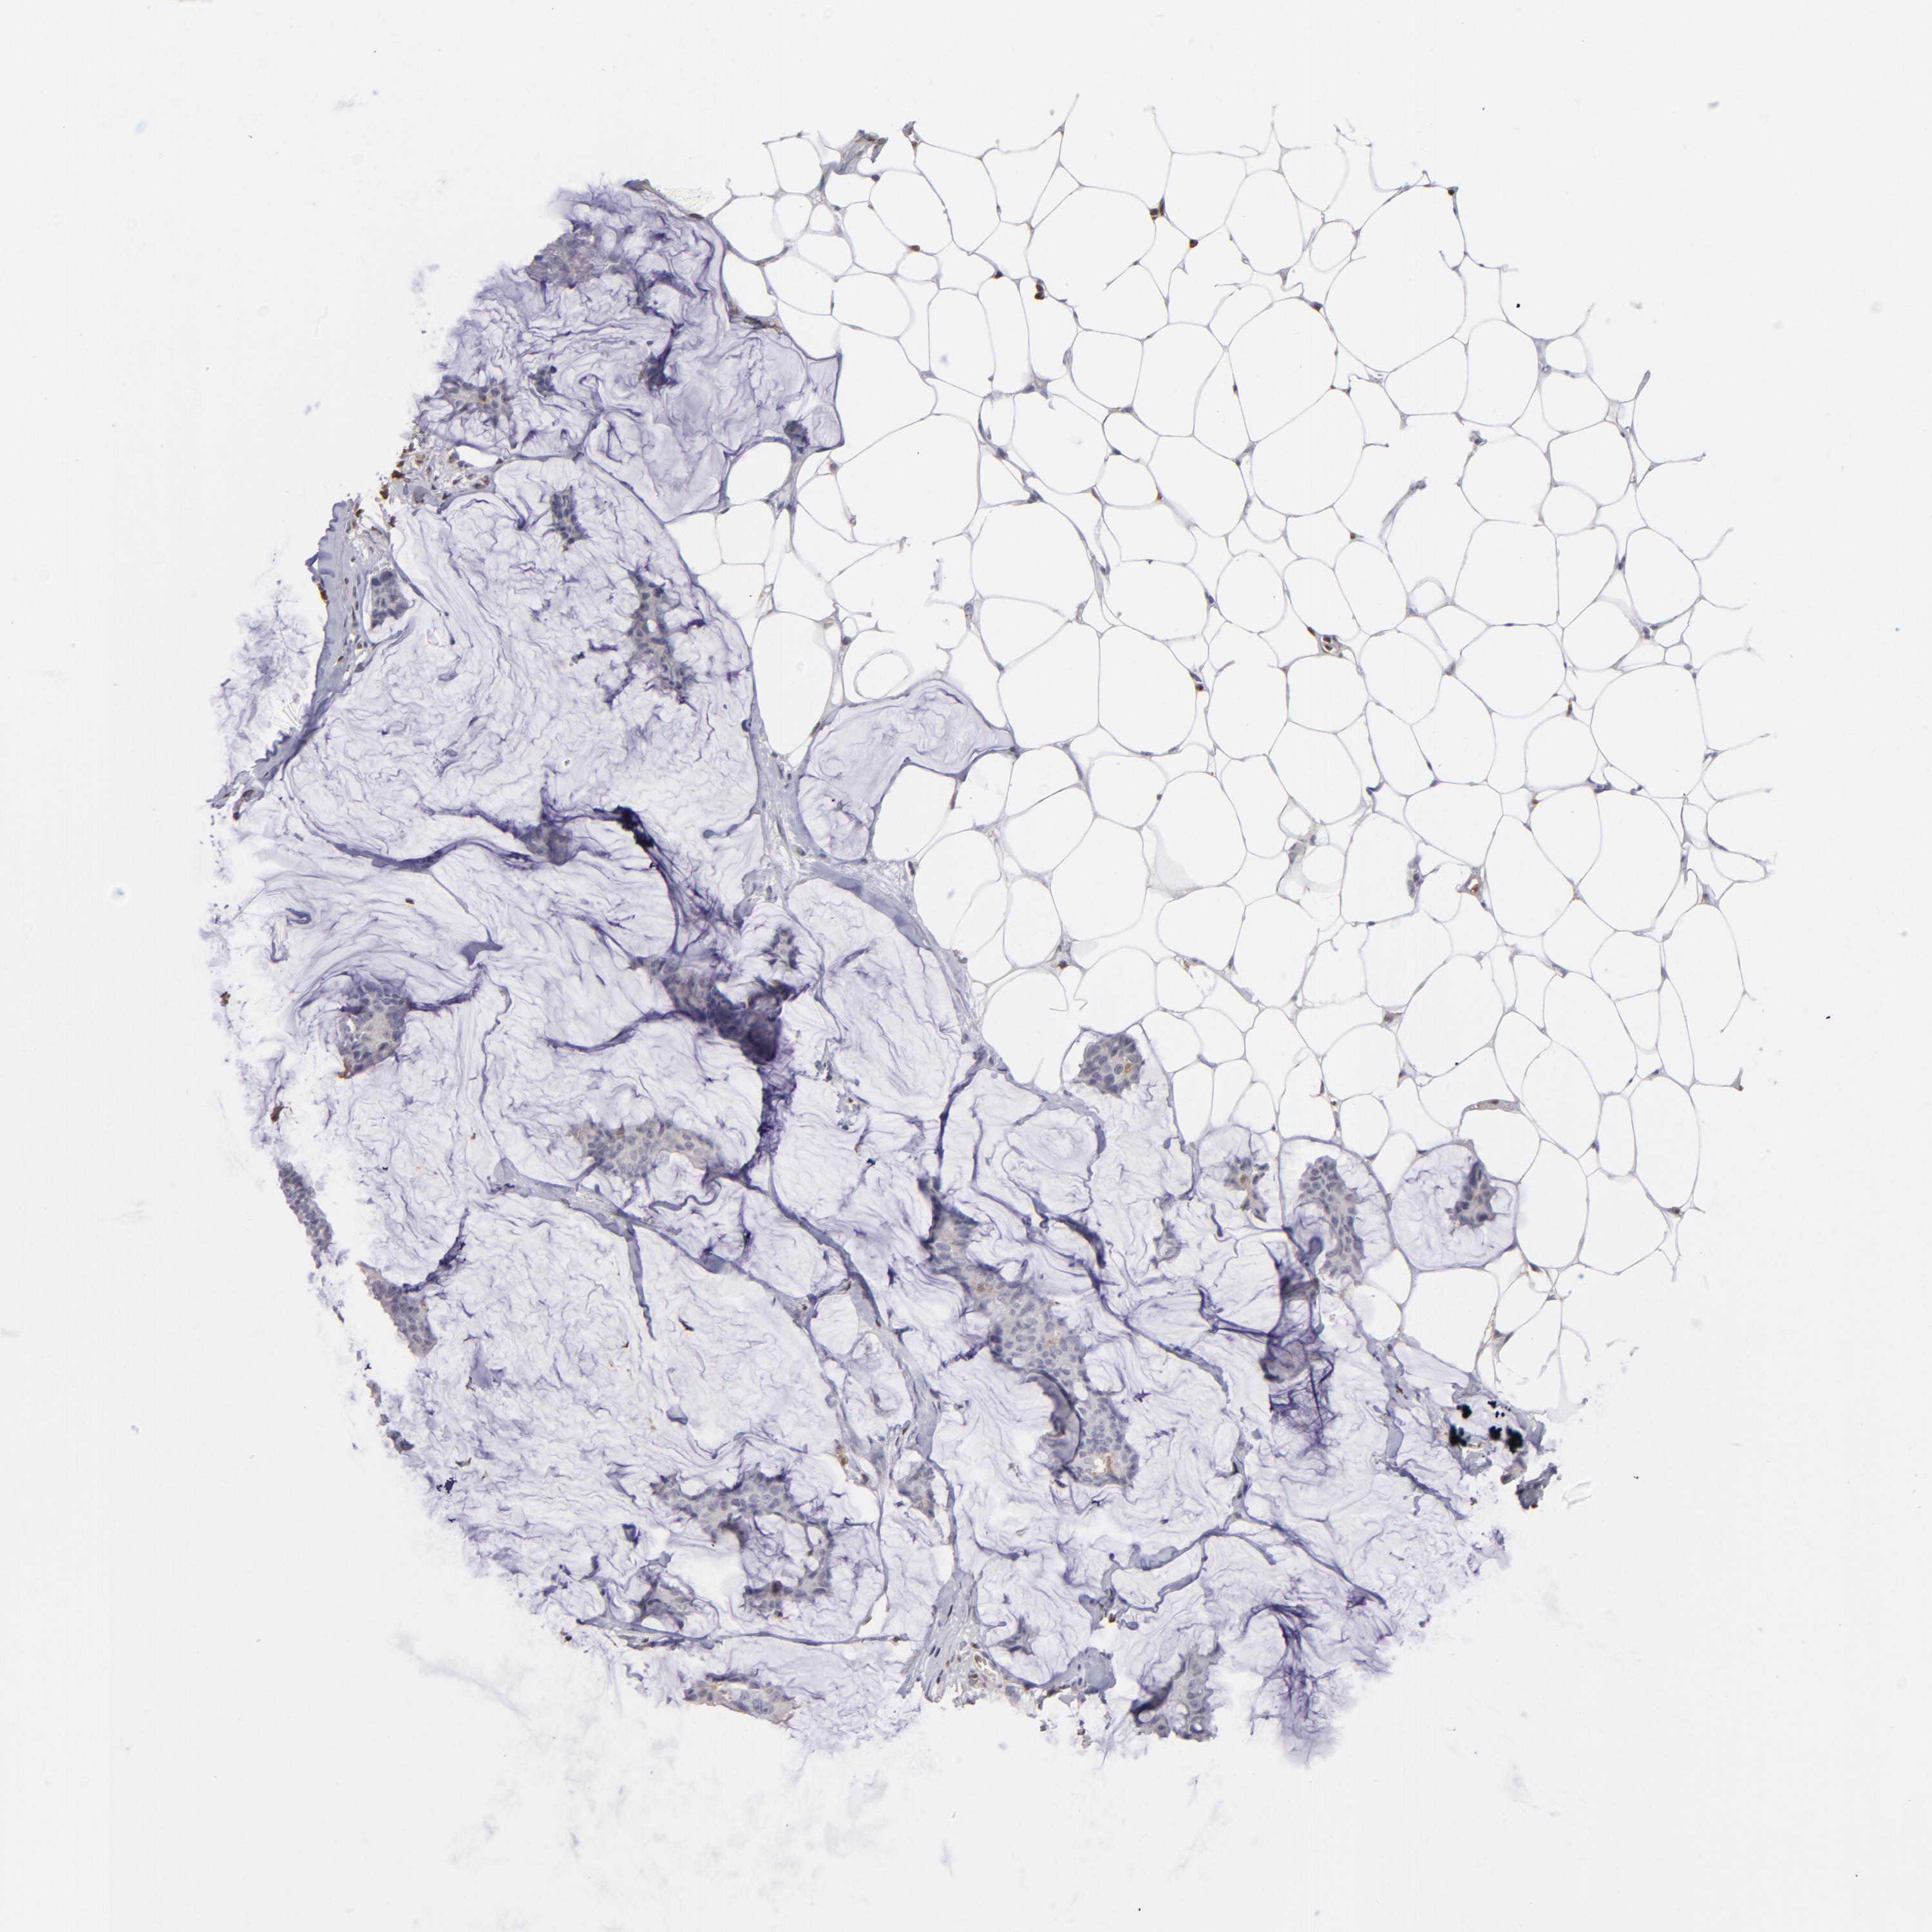

CANCER BREAST CANCER Show tissue menu

BRCA TCGA BRCA VALIDATION PROTEIN EXPRESSION

ANTIBODIES

AND

VALIDATION